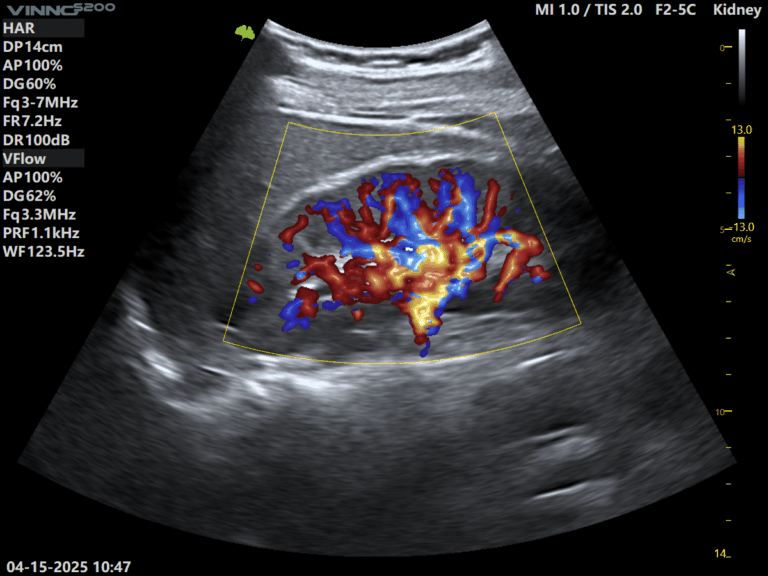

- Functii avansate precum module cu AI, elastografie si Doppler color de inalta rezolutie

- Imagini clare 2D si evaluare precisa a fluxului sanguin